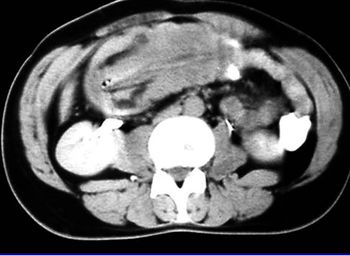

Patient swallows multiple foreign bodies.